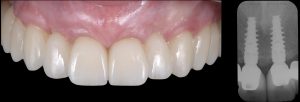

Muco-integration of dental implants for long-term tissue health and stability